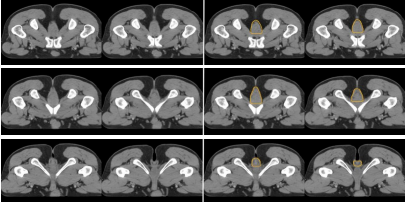

b) 直腸系膜區-M(深綠) (圖 7),邊界:

上界:腸系膜下動脈分叉為乙狀結腸動脈與直腸上動脈處/直乙交界;

下界:肛提肌插入外括約肌處/直腸周圍系膜脂肪組織消失處;

前界上:直腸上動脈前緣擴 0.7 cm;

前界中/下:直腸系膜筋膜,前方盆腔器官的后界;

后界:盆腔骶前區的前界;

外界上:側方、髂外淋巴結區的內側;

外界中:直腸系膜筋膜,側方淋巴結區的內側;

外界下:肛提肌內側緣。

圖 7  直腸癌直腸系膜區 CTV 勾畫示例